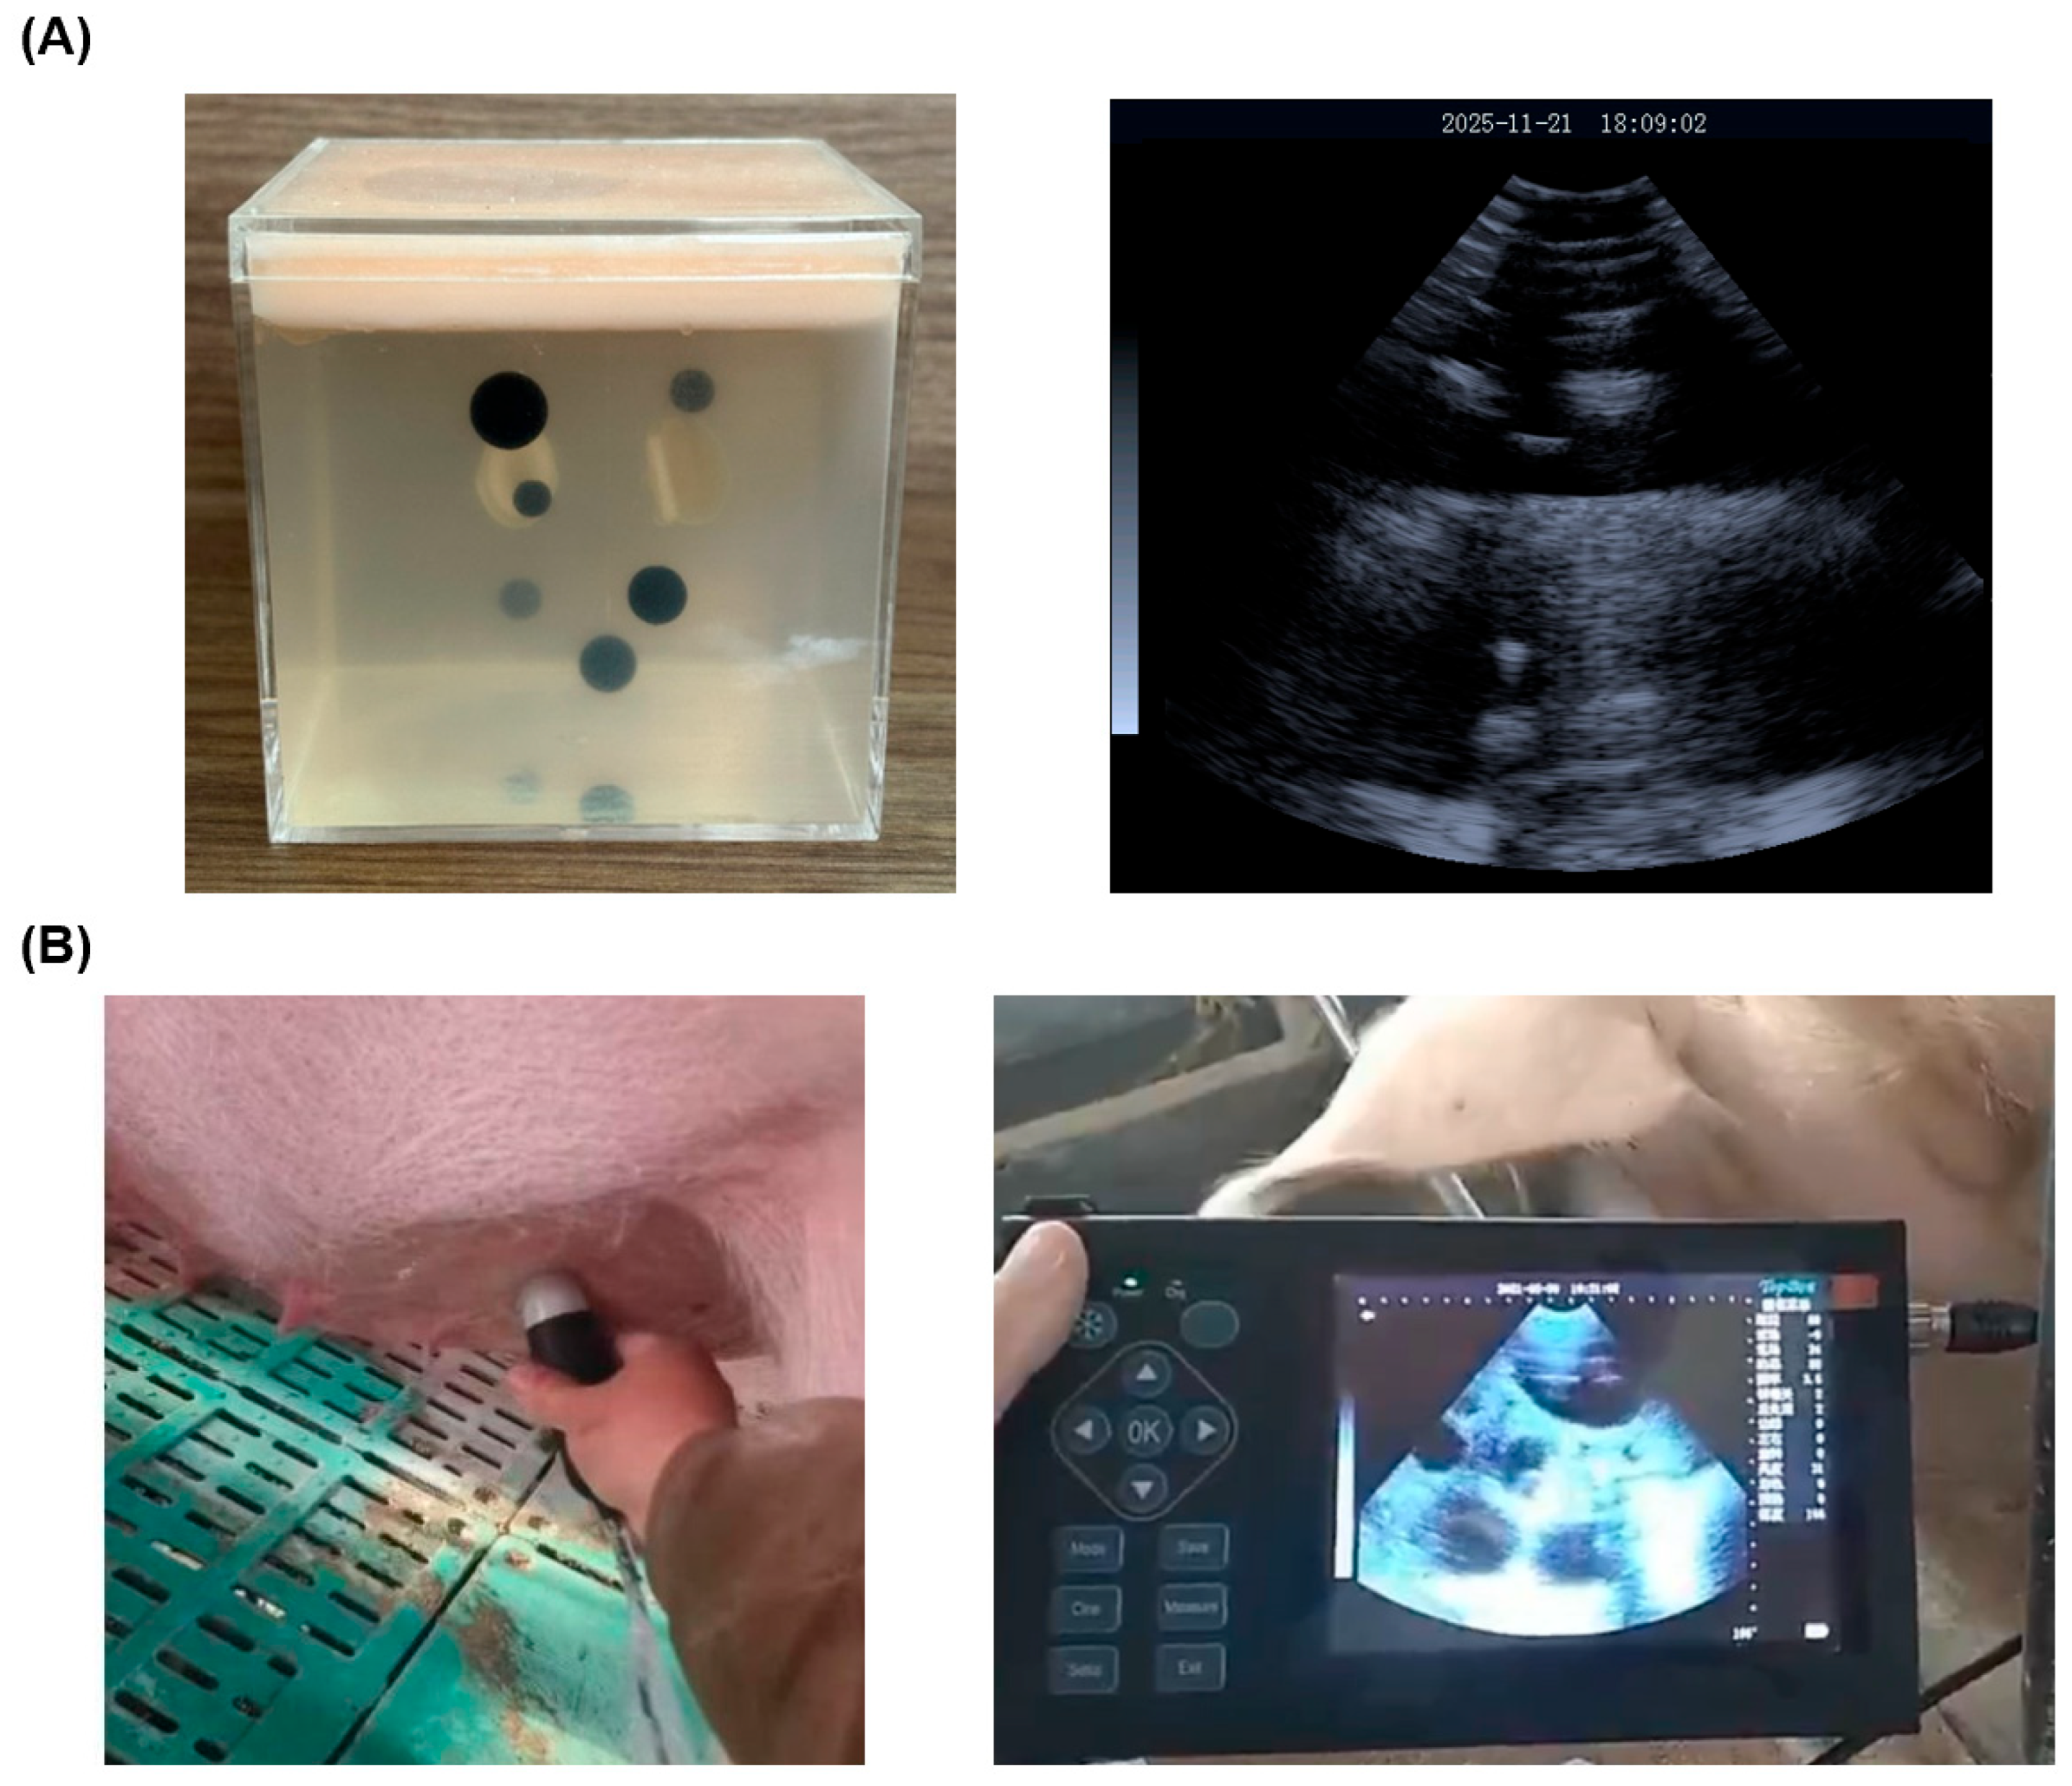

2. Experimental Section: System and Principles

2.1. The Ultrasonic Biosensing System: An Overview

2.2. Principles of the Ultrasonic Biosensor

2.3. Biosensor Hardware: Mechanical Sector-Scanning Probe

3.1. Dataset Construction and Enhancement for Robust Training